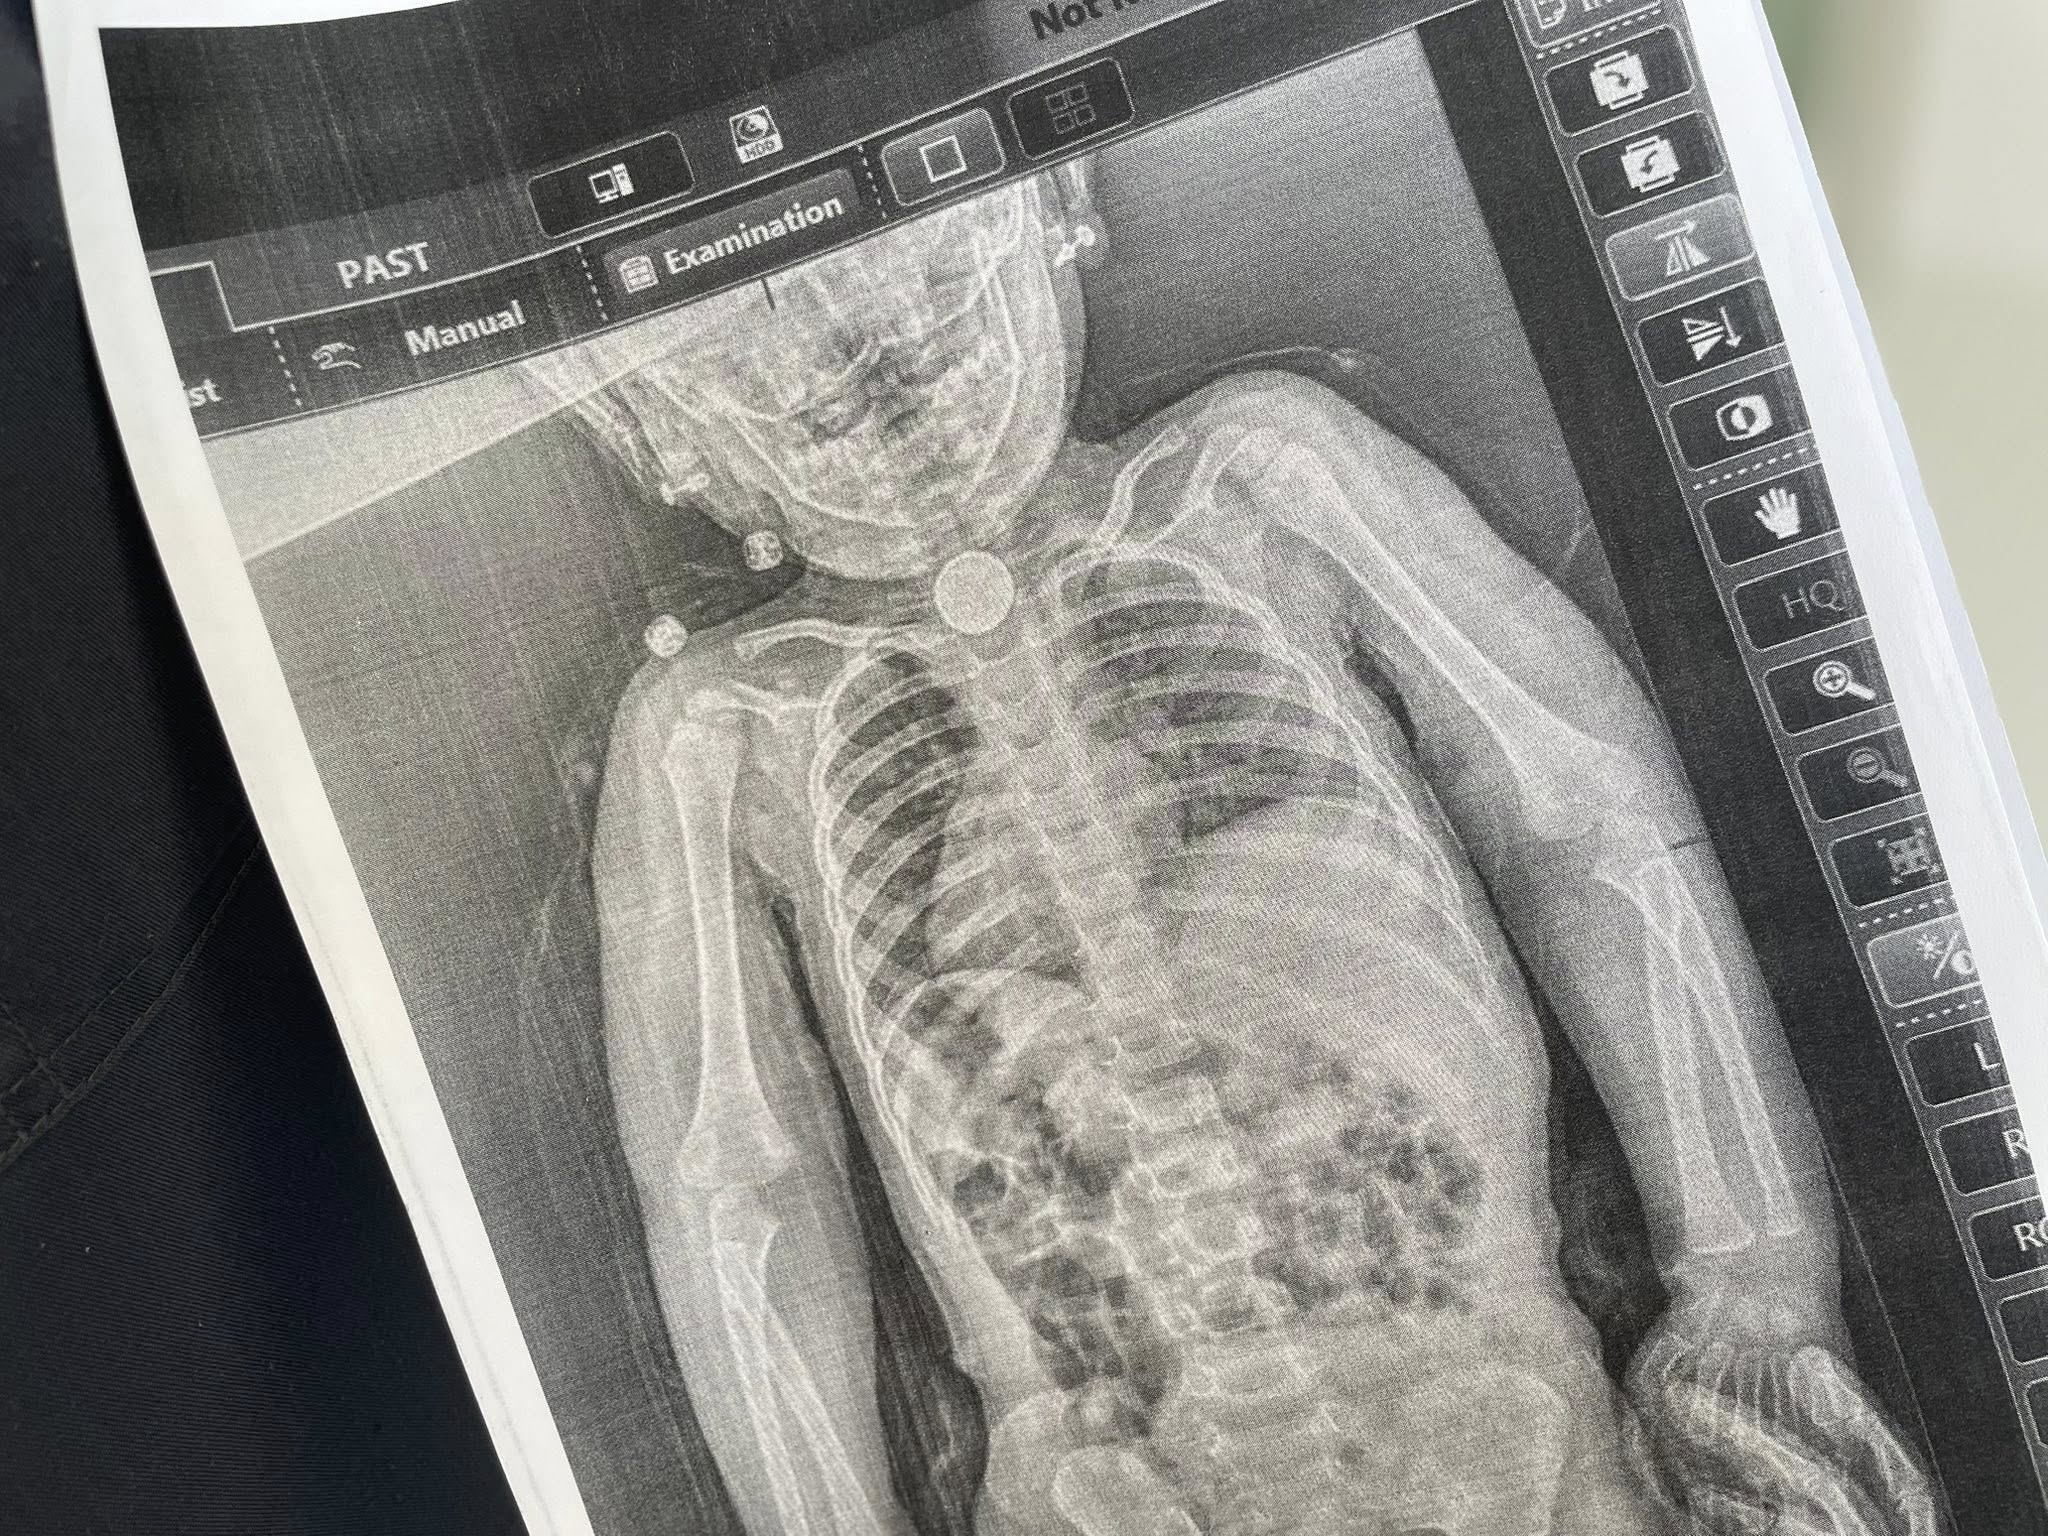

Батьки знову повезли доньку до лікарні та наполягли на додатковому обстеженні. Рентгенівський знімок допоміг нарешті з'ясувати – у стравоході дитини був сторонній предмет.«Уже під час ендоскопічного обстеження точно встановили, що це було. У ділянці першого фізіологічного звуження стравоходу міцно застрягла кругла літієва батарейка діаметром 2,5 см. Навколо неї сформувалися набряк та гіпергрануляції слизової оболонки – ознаки тривалого ушкодження тканин», – розповіли у лікарні Святого Миколая.